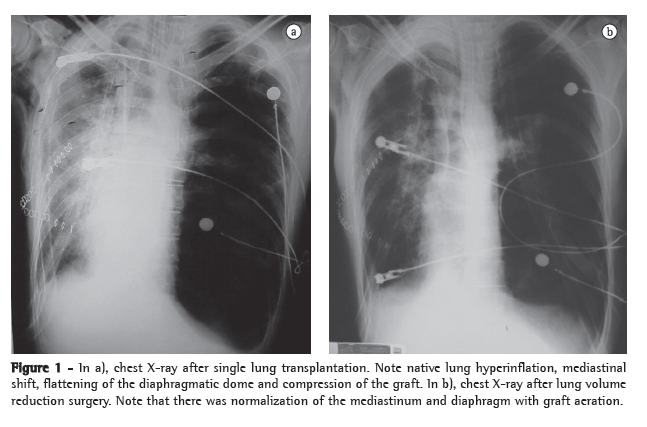

After 7 months on a waiting list, the patient underwent single right lung transplantation, in which the duration of ischemia was 210 min. Immunosuppression was performed with azathioprine, cyclosporine and methylprednisolone. The patient was referred to the ICU and remained intubated for 5 days. However, he developed respiratory failure and required reintubation. There was progressive native lung hyperinflation, with mediastinal shift and worsening of the respiratory pattern. Independent ventilation was employed but did not result in radiological or clinical improvement (Figure 1).

The patient underwent left lung volume reduction surgery to prevent compression of the graft. A linear cutting stapler was used, and multiple wedge resections were performed. Approximately 20% of the parenchyma in the lung apex was removed. The mechanical suture line was reinforced by interposing bovine pericardial tissue, as previously described by Cooper.(8)

There was radiological improvement, with expansion of the graft and normalization of the diaphragmatic contour, as well as improvement in pulmonary function (Figure 1). However, the patient developed dehiscence of the anastomosis of the anterior wall of the right main bronchus, together with bronchopleural fistula. The consequent empyema and sepsis led to his death on postoperative day 16.